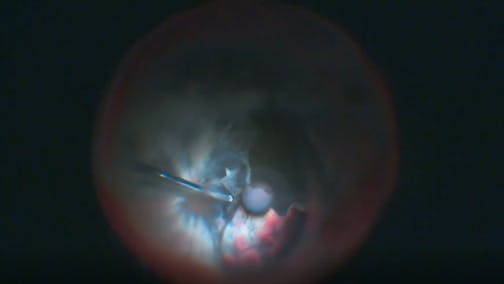

Optic Nerve Pit

Kourous A. Rezaei, MD